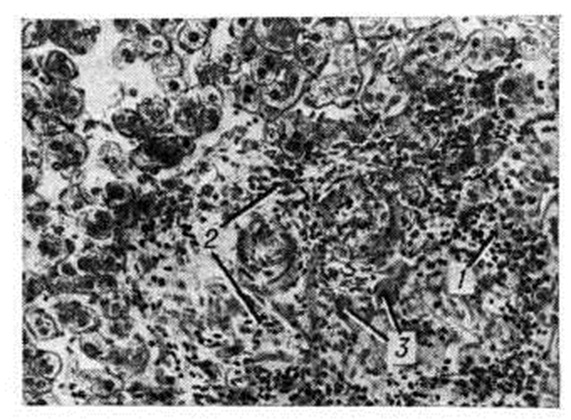

Рис. 2.

Микропрепарат печени при саркоидозе, осложнённом хроническим гранулематозным гепатитом: в паренхиме дольки видна узелковая (бугорковая) реакция из лимфоидных (1) и эпителиоидных (2) клеток с примесью гигантских клеток (3); окраска гематоксилин-эозином; × 140.